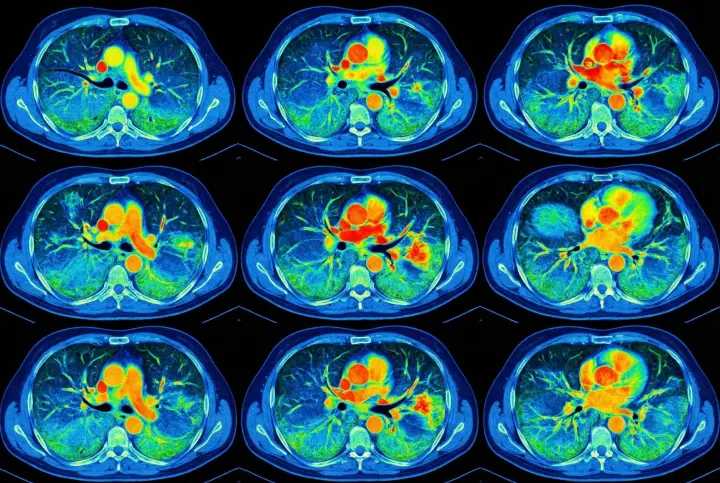

1. Severe lung damage - a life without breath

Over time, chronic inflammation and toxin buildup cause irreversible damage to the airways and lung tissue.

The lungs lose their ability to absorb oxygen efficiently. No quick remedy can restore what's been destroyed.

2. COPD progression - the silent suffocator

Untreated lung congestion and airway inflammation often develop into full-scale COPD.

It may begin with mild shortness of breath or an occasional cough-but the damage continues silently.

Before patients realize what's happening, their lung capacity has already declined significantly.

3. Oxygen deprivation leading to chronic fatigue

As lung function deteriorates, oxygen levels in the body drop.

The result is constant exhaustion, weakness, and overwhelming fatigue.